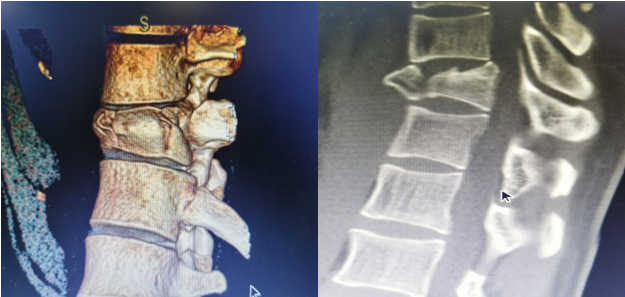

11月7日上午11时,省中医医院急诊室送来了一位32岁的小伙,于我院施工干活时不慎从高处意外坠落受伤,病情危急。急诊科、创伤中心张选国主任接诊后,患者病情危重,痛苦不堪。张选国主任和同事们立马启动绿色通道,准备各项救治措施,快速完善初步检查后,提示胸椎爆裂骨折。“立马打电话请骨二科王主任紧急会诊”。王彦鹏主任会诊后意见,患者为高空坠落伤,胸11椎体爆裂性骨折,骨折很不稳定,骨折片容易侵入椎管及主要血管,并发截瘫概率高。立刻收住院,完善检查后行手术治疗。

术前

入院后,经过全面的病情评估,一方面要尽快开展手术,另一方面要确保手术安全,经过骨二科全健主任医师、王彦鹏副主任医师团队及麻醉科主任于军主任及手术室荣华护士长充分讨论后,决定行“胸11椎体爆裂骨折椎弓根螺钉复位内固定术”。经过团队的奋战,手术顺利完成,效果满意。

术后椎体高度恢复满意